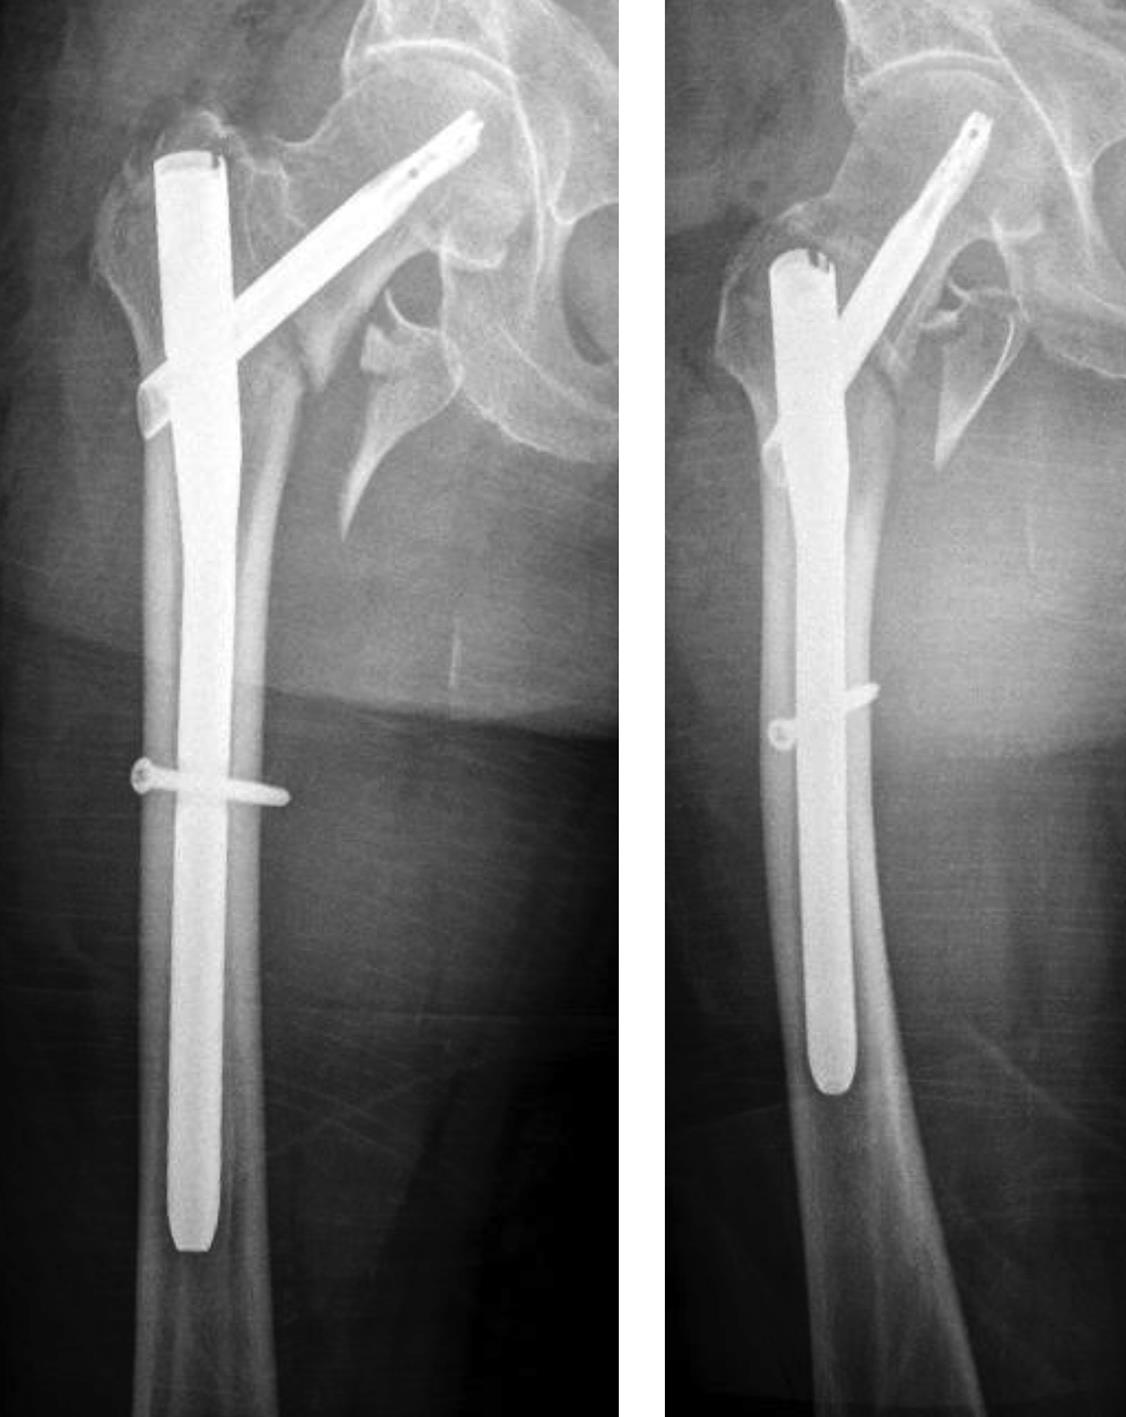

An 83-year-old female patient sustained a 31-A.2.2 fracture of the right proximal femur after a fall at home (Figs 1-2). Intraoperative and postoperative images are shown (Figs 3-5).

Case provided by Michael Blauth, Innsbruck, Austria